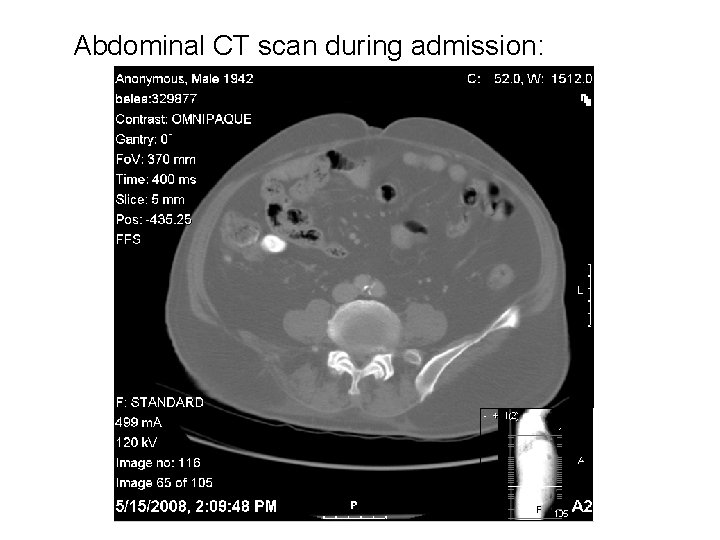

Abdominal CT scan during admission: